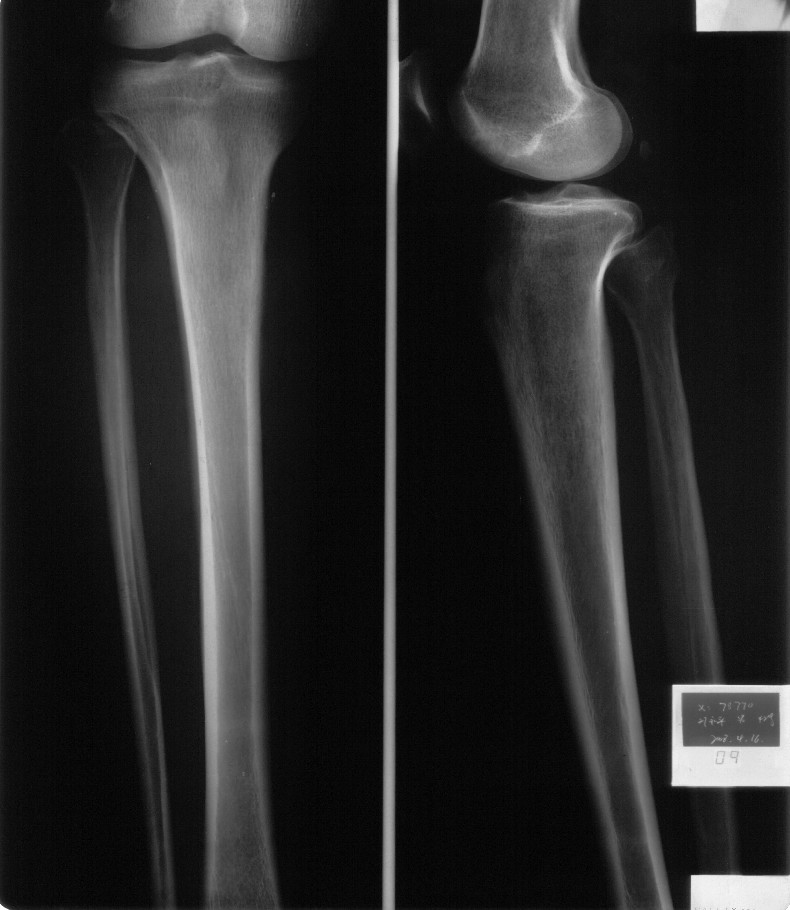

男,42岁。4个月前钢筋钝伤右侧小腿部,当时因无明显外伤,未引起重视。一周后因受伤腿部疼痛,发现肿胀,随后到当地医院进行检查(2008年4月16日)。因未发现骨质异常未引起重视,仅仅进行口服抗生素治疗处理。经过一段时间治疗但未见明显治疗效果在5月29日又进行x线检查,发现有胫骨密度上段密度增高,又进行抗炎治疗,仍未见效果。又在7月3日进行x线检查,仍然报告有胫骨上端密度增高,并建议ct检查。以下是相关检查结果: